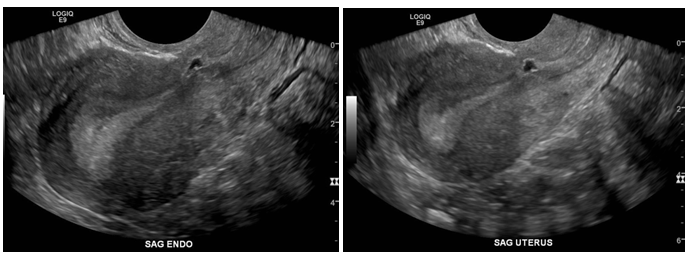

The REI workup included ultrasound, hysterosalpingogram (HSG), MRI and hysteroscopy with lysis of adhesions, and endometrial sampling for evaluation of failed intrauterine insemination, 6 months prior to referral. The initial ultrasound showed mucus accumulation and free fluid in the uterus (Figure 1). Hysteroscopy revealed a small out-pouching in the lower anterior uterine segment. A subsequent MRI in our clinic confirmed both the ultrasound and Hysteroscopic findings, revealing a small CSD, (Figure 2) for which she desired surgical correction.

Figure 1 Patient 1, Ultrasound: Ultrasound on 6/3/17, showing Mucus accumulation and free fluid in the uterus as well as a scar defect in anterior uterine wall (Red Circle).